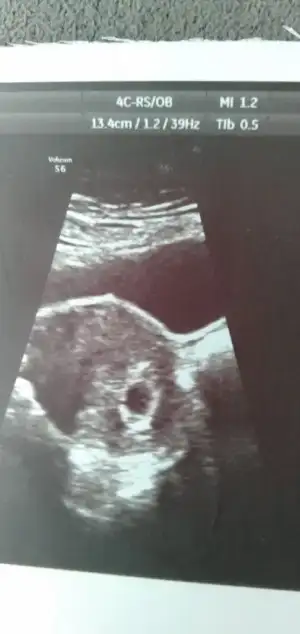

Merhaba 7+4 karından bakıldı cinsiyet yorumlar mısınız ?

Eklentiler

• 45F5D451-8E5E-478A-BBC1-0AB0FA1AEE6F.webp

45F5D451-8E5E-478A-BBC1-0AB0FA1AEE6F.webp

17,2 KB · Görüntüleme: 132